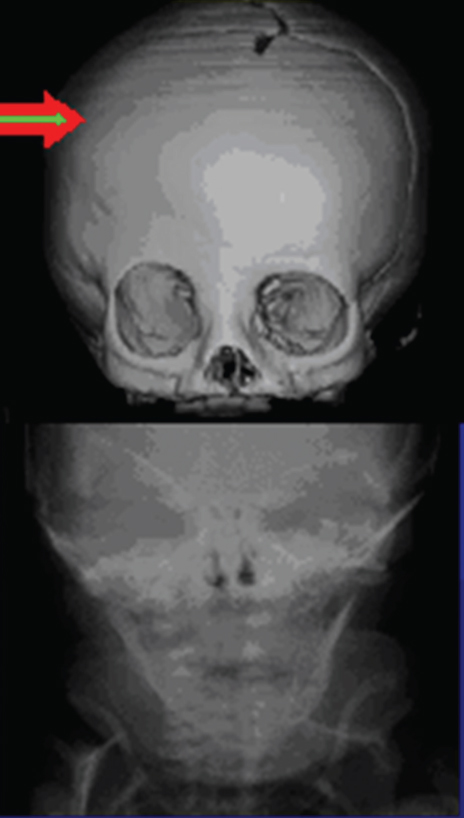

Unilateral and bilateral coronal synostoses are recognized by their forehead deformities ( Fig. 66.4 ). These are termed the anterior plagiocephalies. Bilateral coronal sysnostosis cases present with a symmetric short and tall skull termed turribrachycephaly. Cranial index in these patients will be elevated >82 to 85; patients with an index greater than 85 have severe brachycephaly. Unilateral coronal sysnostosis cases are often the most difficult to treat and present with varying degrees of frontofacial dysmorphology including an ipsilateral retruded brow and raised eyebrow. Growth arrest along the squamosal suture line resulting in the characteristic radiograph finding of a harlequin deformity is diagnostic. Often the contralateral forehead will be significantly bossed, accentuating the frontofacial asymmetry.

Radiologic studies are seldom needed for initial diagnosis of cranial deformities, 52 , 53 although imaging technology plays a key role in treatment decisions and preoperative planning. CT imaging and threedimensional reconstruction provide detailed information about the cranial anatomy and sutures that cannot be obtained with routine radiographs. Preoperative modeling based off of CT imaging will play an ever-increasing role in the treatment of congenital craniofacial anomalies. Computerguided planning has the potential for reduced operative times and more precise reconstructions based off of cephalometric norms. Plain films have little role in the treatment and diagnosis of children with craniosynostosis. Also, CT imaging is not without its own risks; while protocols are still being perfected to reduce radiation exposure, every effort should be made to limit the number of imaging studies. Frequently, a single threedimensional CT within a month of a reconstructive operation is recommended. If imaging studies are preformed too early during this period of significant calvarial growth, the imaging study will lose its utility as a preoperative guide. Less invasive interventions, such as endoscopic craniectomies and suturectomies, may be performed without preoperative CT scans.

The CT evaluation reveals the amount of asymmetry of the skull and the compensatory changes that have occurred; in addition, it allows for identification of the venous sinuses. 54 , 55 The largest risk factor in these operations is blood loss and a clear knowledge of the position of the torcula helps prevent inadvertent injury in low posterior remodeling procedures. The CT scan in occipital deformities may also indicate abnormalities of the brain and the bone. Infants with severe deformities typically show diminished posterior subarachnoid fluid similar to the changes seen with increased ICP, but on a more localized basis. This appears to extend into the ventricular system, resulting in ventricular effacement. Generalized subarachnoid space dilation per se anteriorly does not indicate neurologic impairment, for it frequently is found in posterior plagiocephaly with normal neurologic status. With severe compression, sometimes the ipsilateral perimesencephalic cistern is effaced also. The finding usually correlates with an irregular, patchy, diminished thickness of the occipital bone. The patchiness is greatest in bilateral cases and appears to be similar to the copper-beaten or thumbprinting appearance seen on plain radiographs. “Copper beating” may not be a good marker for raised ICP because it occurs late and is an inconsistent finding. 56